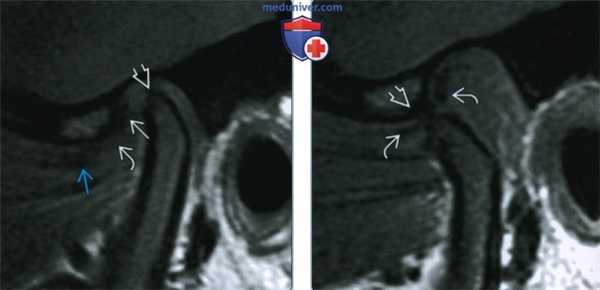

(Слева) На косой сагиттальной МРТ (Т1 ВИ) ВНЧС с закрытым ртом визуализируется задний пучок диска, находящийся в нормальном положении относительно мыщелка.

(Справа) На косой сагиттальной МРТ (Т1 ВИ) ВНЧС у этого же пациента визуализируется задний пучок диска, остающийся спаянным с самыми верхними отделами суставной ямки. Область соединения переднего пучка с переходной зоной находится между мыщелком и суставным возвышением. Отсутствует трансляция диска относительно заднего ската суставного возвышения.

(Слева) На косой сагиттальной МРТ (Т2 ВИ) левого ВНЧС с закрытым ртом визуализируются задний пучок и переходная зона диска, нормально расположенные относительно мыщелка.

(Справа) На косой сагиттальной МРТ (Т2 ВИ) с открытым ртом у этого же пациента определяется ограничение трансляции мыщелка. Отсутствует трансляция диска по заднему скату суставною возвышения. Задний пучок диска занимает наиболее высокое положение в суставной ямке. Область соединения переходной зоны и переднею пучка находится между мыщелком и суставным возвышением.

(Слева) При МРТ Т1 в сагиттальной проекции определяется смещение суставного диска кпереди: задний валик диска смещен кпереди от мыщелка, промежуточная зона диска истончена, передний валик диска деформирован. Обратите внимание на истончение кортикального слоя и уплощение суставной поверхности мыщелка.

(Справа) При МРТ Т1 в сагиттальной проекции в положении пациента с открытым ртом видно, как мыщелок заходит на суставной бугорок и происходит репозиция суставного диска. Такие случаи смещения суставного диска вперед называют смещением диска с редукцией.

(Слева) При МРТ Т1 в сагиттальной проекции отмечается деформация суставного диска Ш, полностью смещенного вперед относительно мыщелка нижней челюсти. Обратите внимание на уплощение и клювообразную деформацию передней части мыщелка нижней челюсти.

(Справа) При МРТ Т1 в сагиттальной проекции в положении с открытым ртом наблюдается смещение мыщелка к суставному бугорку, но при этом диск остается спереди от мыщелка - наблюдается смещение диска вперед без редукции.